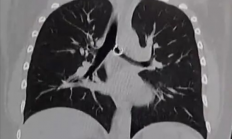

快科技4月16日消息,去年底,26岁墨西哥TikTok博主莫妮卡・德亚尼拉・卡布雷拉・巴拉哈斯在鬼门关里走了一遭,近日有海外媒体详细报道了此事。她因持续咳嗽一个月不见好转,前往医院检查后,竟发现肺中藏着一枚自己丢失的鼻环,而这枚鼻环距离肺主...